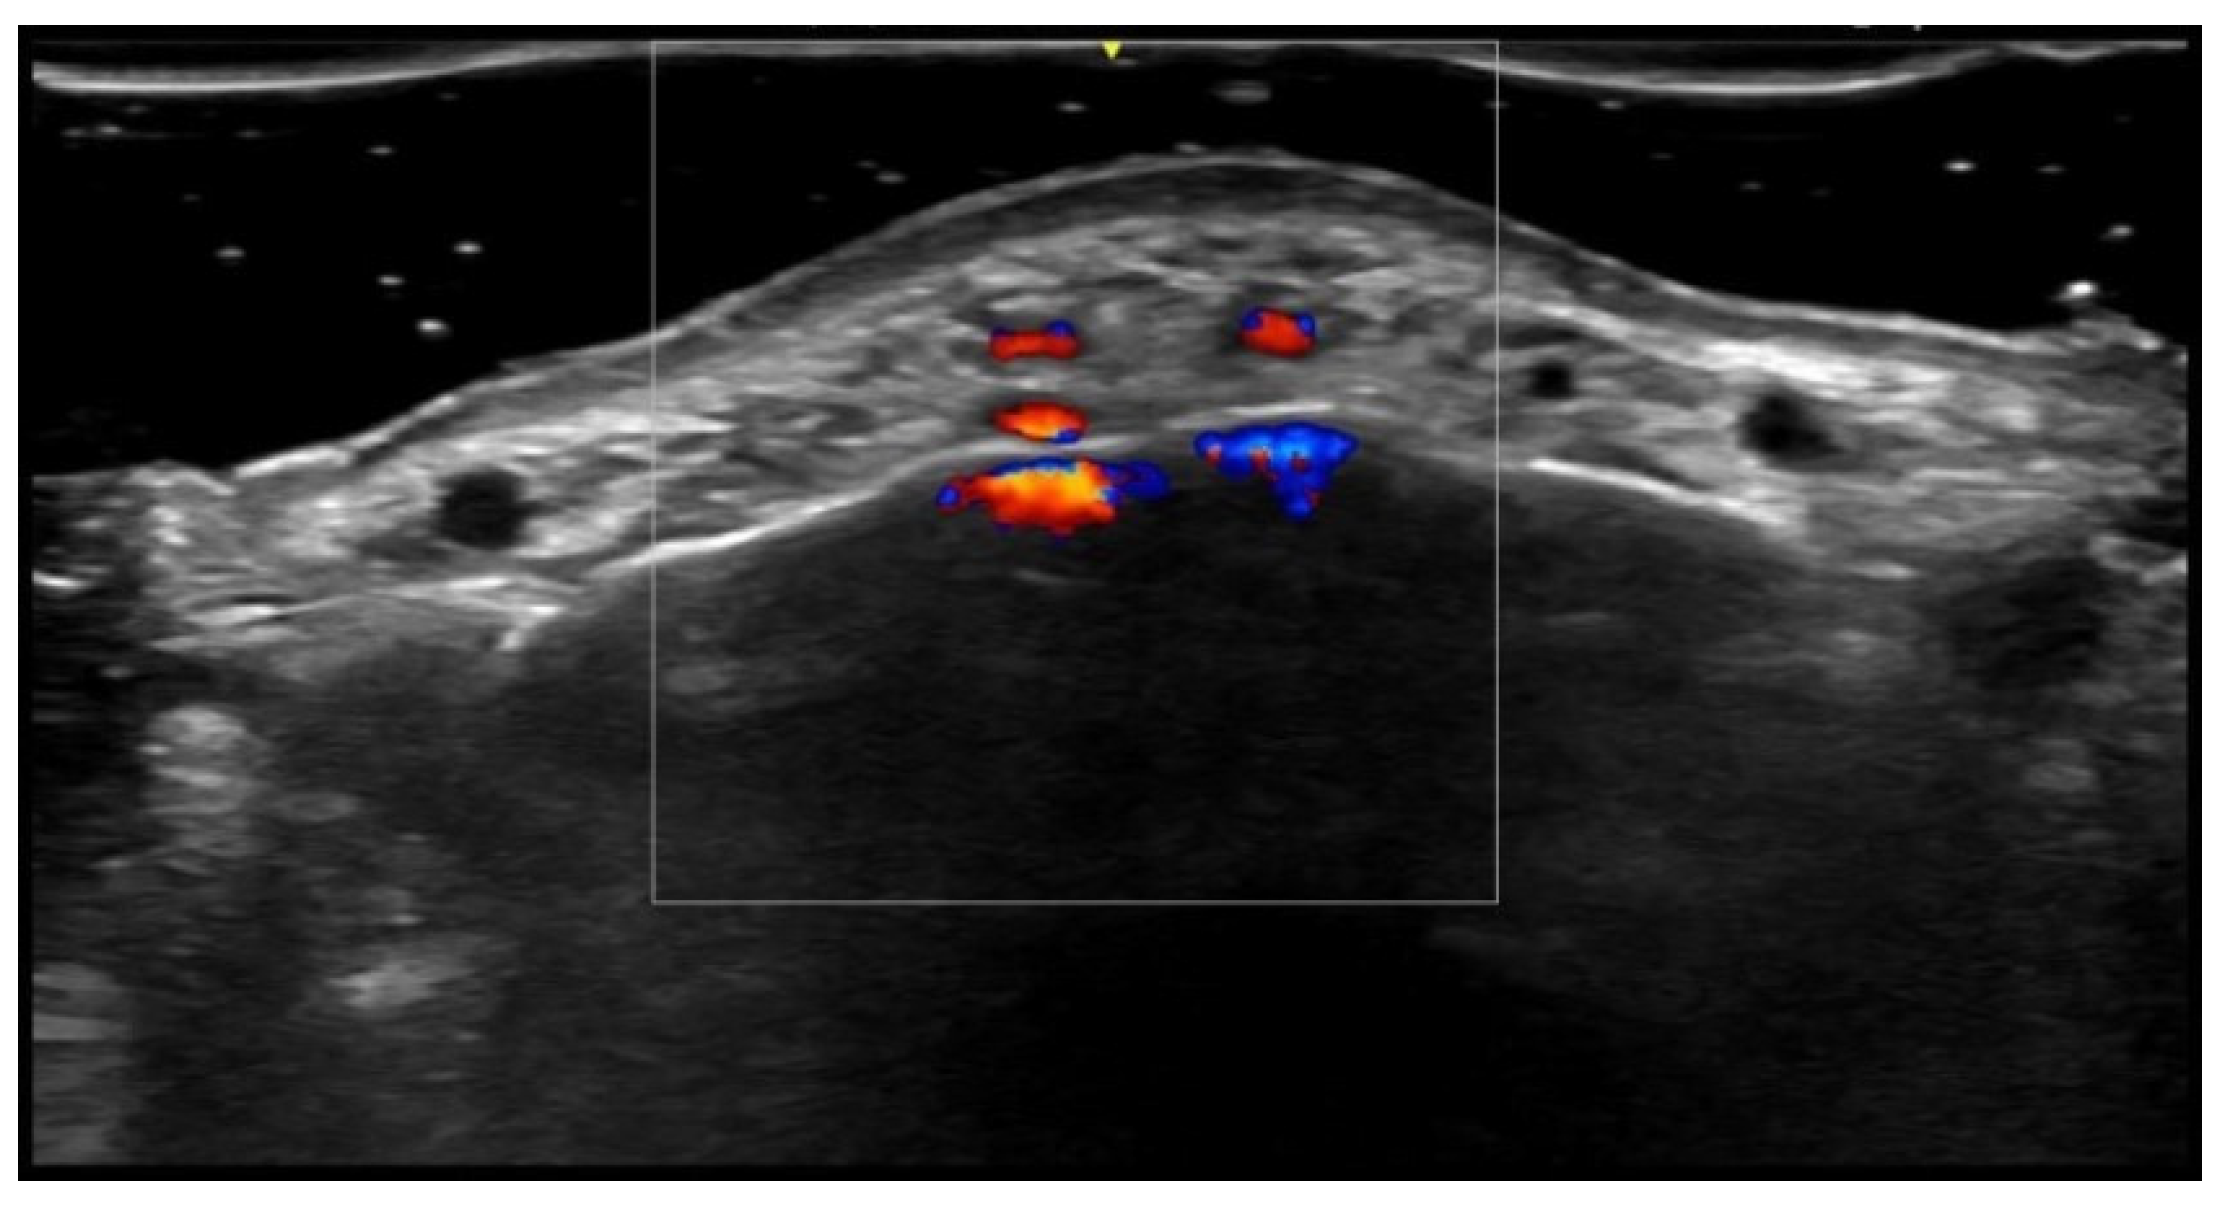

5. Specific Cutaneous Structure and Sites of Skin Disorders